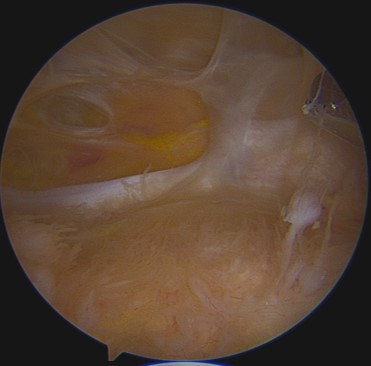

脂肪幹細胞如何取得

通常是從患者的腹部脂肪,在無菌技術操作下,採局部麻醉。取脂肪的過程大约需要 60 分鐘。有專門設計的工具用於採集新鮮活的脂肪细胞。術後不適感極小,也沒有活動上的限制。